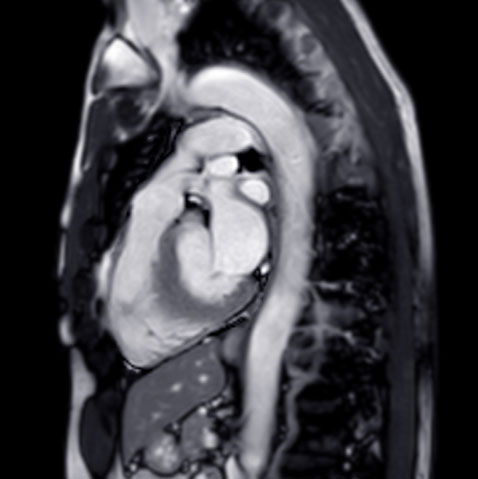

Ascending thoracic aortic disease is an important cause of sudden death in the U.S., yet most aortic aneurysms are identified incidentally. To improve assessment of patients who may be at risk for aortic dissection and rupture, researchers from UC San Francisco have developed a prediction model of aortic diameter to identify asymptomatic individuals with enlarged ascending aortic diameter.

In their study, which was published November 15 in the Journal of the American Medical Association (JAMA), the investigators developed and validated a clinical score to estimate ascending aortic diameter. Their prediction model was based on commonly available clinical covariates to identify symptomatic individuals with enlarged ascending aortic diameter, a risk factor for ascending aortic dissection.

The researchers used data from an ongoing magnetic resonance imaging sub-study of the UK Biobank cohort study, which had enrolled participants from 2006 through 2010. Score derivation was performed in 30,018 participants and internal validation in an additional 6,681people. External validation was also performed in 1,367 participants from the Framingham Heart Study (FHS) offspring cohort who had undergone computed tomography from 2002 through 2005, and in 50,768 individuals who had undergone transthoracic echocardiography in the Community Care Cohort Project, a retrospective hospital-based cohort of longitudinal primary care patients in the Mass General Brigham (MGB) network between 2001-2018.